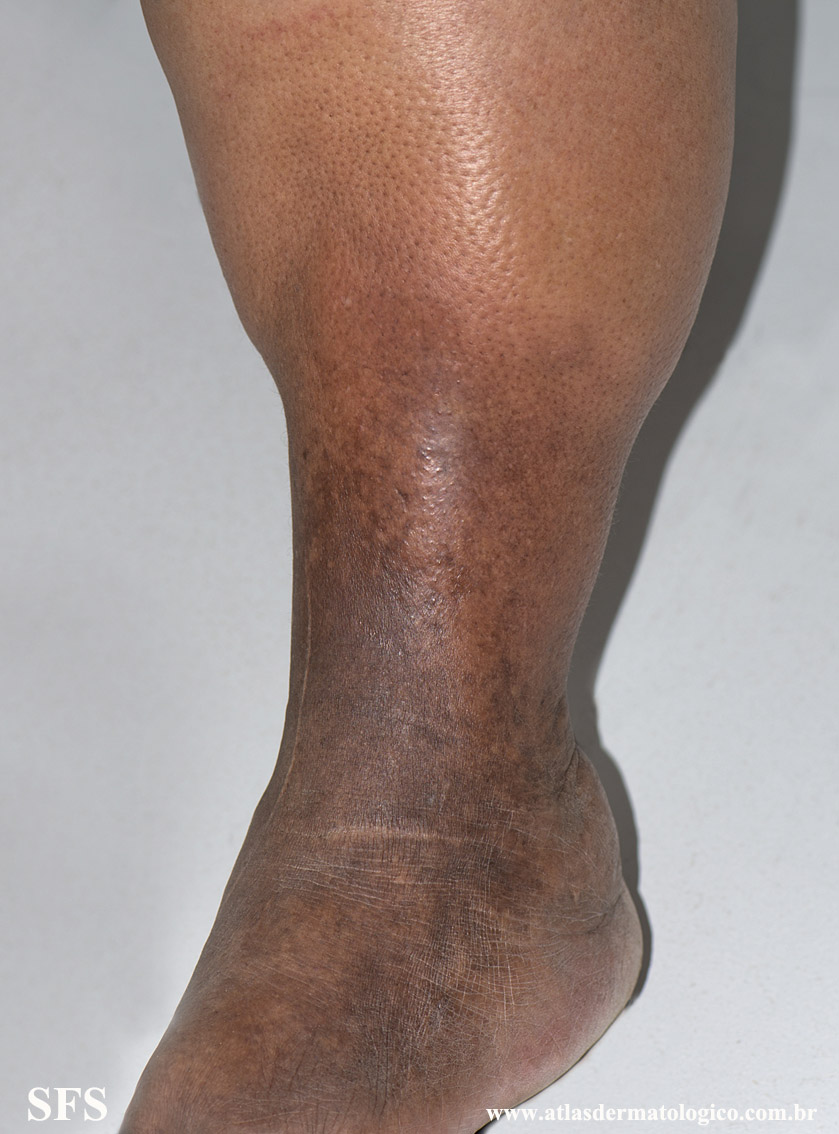

lipodermatosclerosis